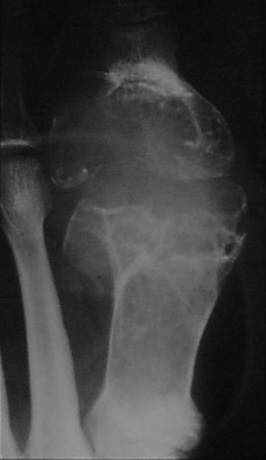

Post traumatic bone lesion

In avulsive lesions of apophysis, the healing phase of the lesion simulates a bone tumor such as pariosteal osteosarcoma (Figure 9ab). This is due to abundant callus and associated calcified hematoma with myositis ossificans. These lesions are well circumscribed without any soft tissue swelling. If one is not familiar with this entity, these may be mistaken for benign or malignant osteogenic tumors. Post traumatic myositis ossificans can occasionally simulate osteochondroma or other benign bone lesion (Figure 9cde). In a bedridden patient due to neurological cause’s dystrophic calcification/ ossification is commonly encountered in the soft tissues particularly in pelvic region which may be mistaken for an osseous tumor such as pariosteal osteosarcoma (Figure 9f).

Figure 9: (a) Avulsion injury at the attachment of rectus femoris to anterior inferior iliac spine, (b) Avulsion injury of the adductors to ischial apophysis. Note the abundant callus and myositis ossificans. (c) Post traumatic myositis ossificans, (d) Exostosis, (e) Myositis ossificans, (f) Pariosteal osteosarcoma.